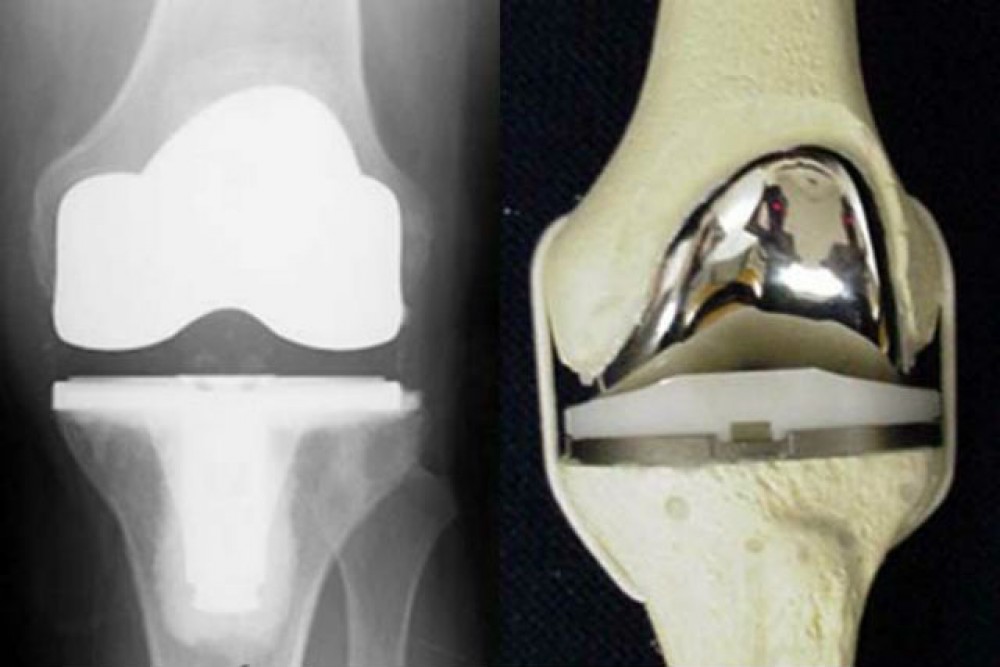

Фотографии и примеры протезирования коленного сустава